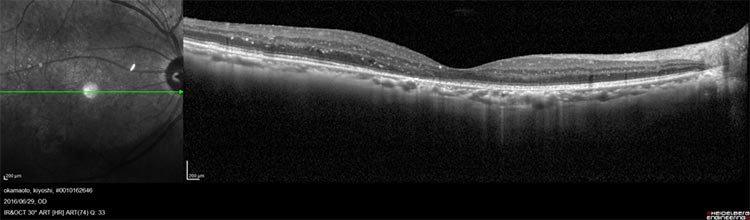

網膜の血管の状態が悪くなると、血管から血液の成分が血管外に漏れ出します。網膜の中心である黄斑部似血液の成分が漏れて貯まると、黄斑浮腫と呼ばれる状態になり、視力が大幅に低下し、ものが歪んで見える(変視症)という症状を来します。逆に黄斑浮腫が出ない場合は、自覚症状が現れにくいです。それでも網膜の毛細血管で糖がだぶつき、これによって同血管が詰まるなどすれば、新生血管が発生し、この脆くて破れやすい血管から血液の成分が漏れる、硝子体内に出血するとなると、飛蚊症(虫が目の前で飛んでいるように見える)、視力低下、霧視などの症状がみられるようになります。さらに放置を続けると網膜表面に増殖膜が張ってきて、網膜剥離を起こし、失明することもあるので要注意です。

診断をつけるための検査としては、主に眼底検査によって、網膜の状態や出血の有無、硬性白斑、新生血管を調べるなどして、判定していきます。

黄斑浮腫は網膜症のどの時期でも発症する可能性がありますが、視力への影響が大きいため、早めに治療を開始します。レーザー、ステロイド・テノン嚢下注射(結膜下への注射)、抗VEGF薬の眼内注射などを行います。